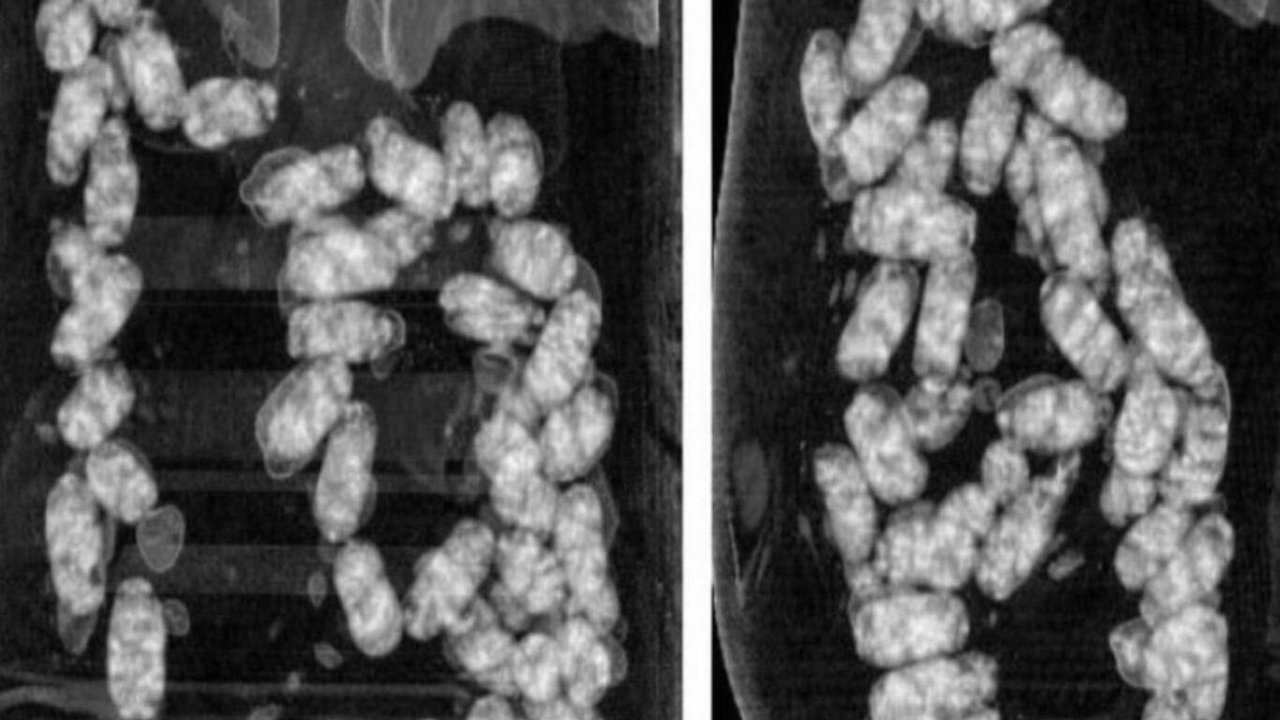

Şüpheliler üzerinde yapılan iç beden muayenesinde, 105 kapsül halinde yutulmuş vaziyette toplam 965 gram metamfetamin ele geçirildi.